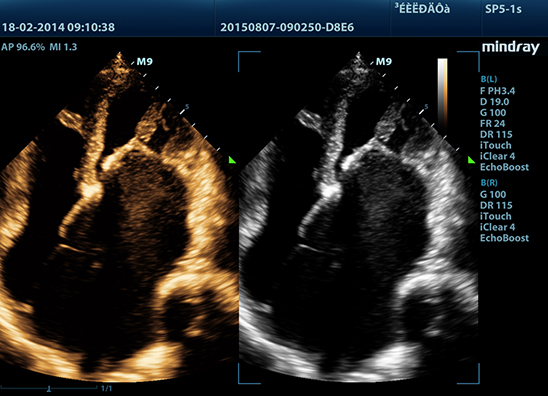

Mindray M9 je dopplerovský ultra ľahký prenosný UZV prístroj najvyššej High End triedy s použitím single crystal 3T sond (vynikajúce zobrazenie blízkeho i vzdialeného poľa), HDR FLOW, ECHO BOOST, Natural Touch Elastography, kontrastného zobrazenia, TDI. Špeciál hlavne pre kardiológiu.

Klinické obrázky: